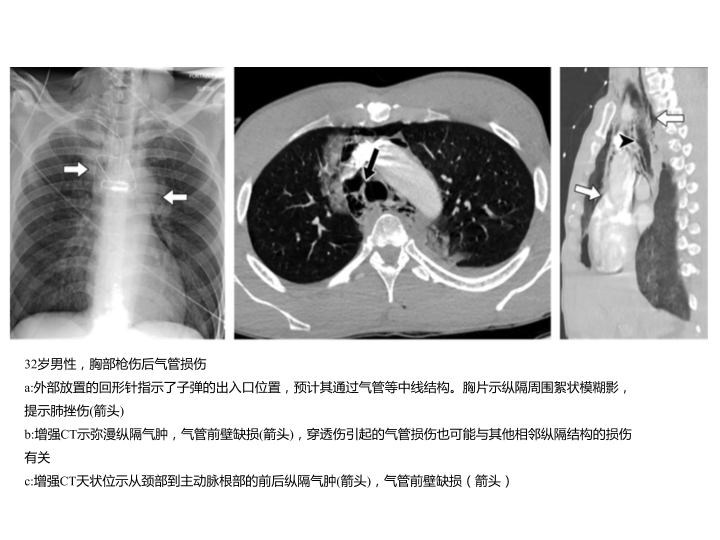

胸部外伤及胸腔积液处理